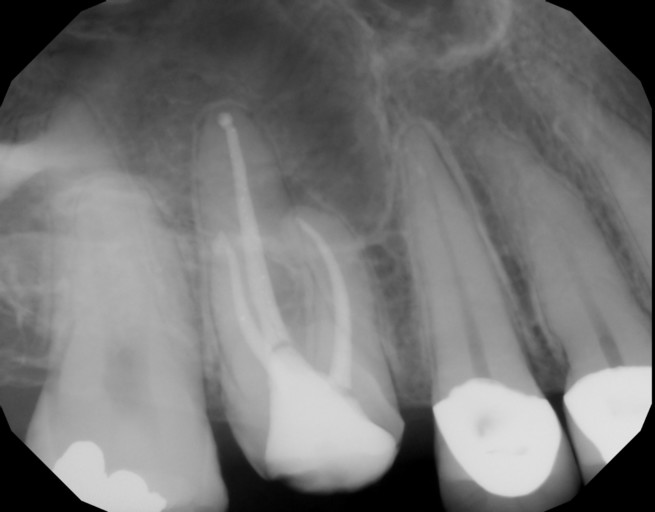

I just went to the dentist because I had fallen and hit my teeth hard. From the X-ray they determined that the nerves in my front two incisors were dead. There was no visible root in either tooth. He didn’t prescribe any treatment because he said the tooth had performed it’s “own root canal”. Is that possible? Should I got back and talk about doing a root canal? There is a little sensitivity in one of the teeth but it’s not debilitating. Should I just wait until the tooth is infected to treat it? I just need some answers. Thanks!

I just went to the dentist because I had fallen and hit my teeth hard. From the X-ray they determined that the nerves in my front two incisors were dead. There was no visible root in either tooth. He didn’t prescribe any treatment because he said...